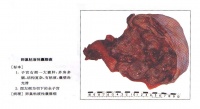

卵巢癌的病理改变[编辑 | 编辑源代码]

卵巢肿瘤卵巢癌病理改变的分类方法很多,本章采纳以组织发生为依据而有临床实用意义的分类。

(一)胚上皮副中肾体腔上皮)来源的卵巢恶性肿瘤 如浆液性腺癌、粘液性腺癌、子宫内膜样腺癌、混合性浆液粘液性囊腺癌、纤维腺癌、恶性勃勒纳氏瘤、副中肾透明细胞癌、未分化(间变性)癌等,这些肿瘤有时有黄素化作用。

(二)胚细胞来源的卵巢恶性肿瘤 如畸胎癌、原发性绒毛膜上皮癌、无性细胞瘤等,有时能分泌激素。

(三)性未分化间叶来源的卵巢恶性肿瘤 如良性瘤1~6同名肉瘤、恶性混合性中胚层瘤、癌肉瘤。

(四)性分化间叶来源的卵巢恶性肿瘤 因具有产生自体激素的功能,又称功能性肿瘤,均属潜在恶性肿瘤。